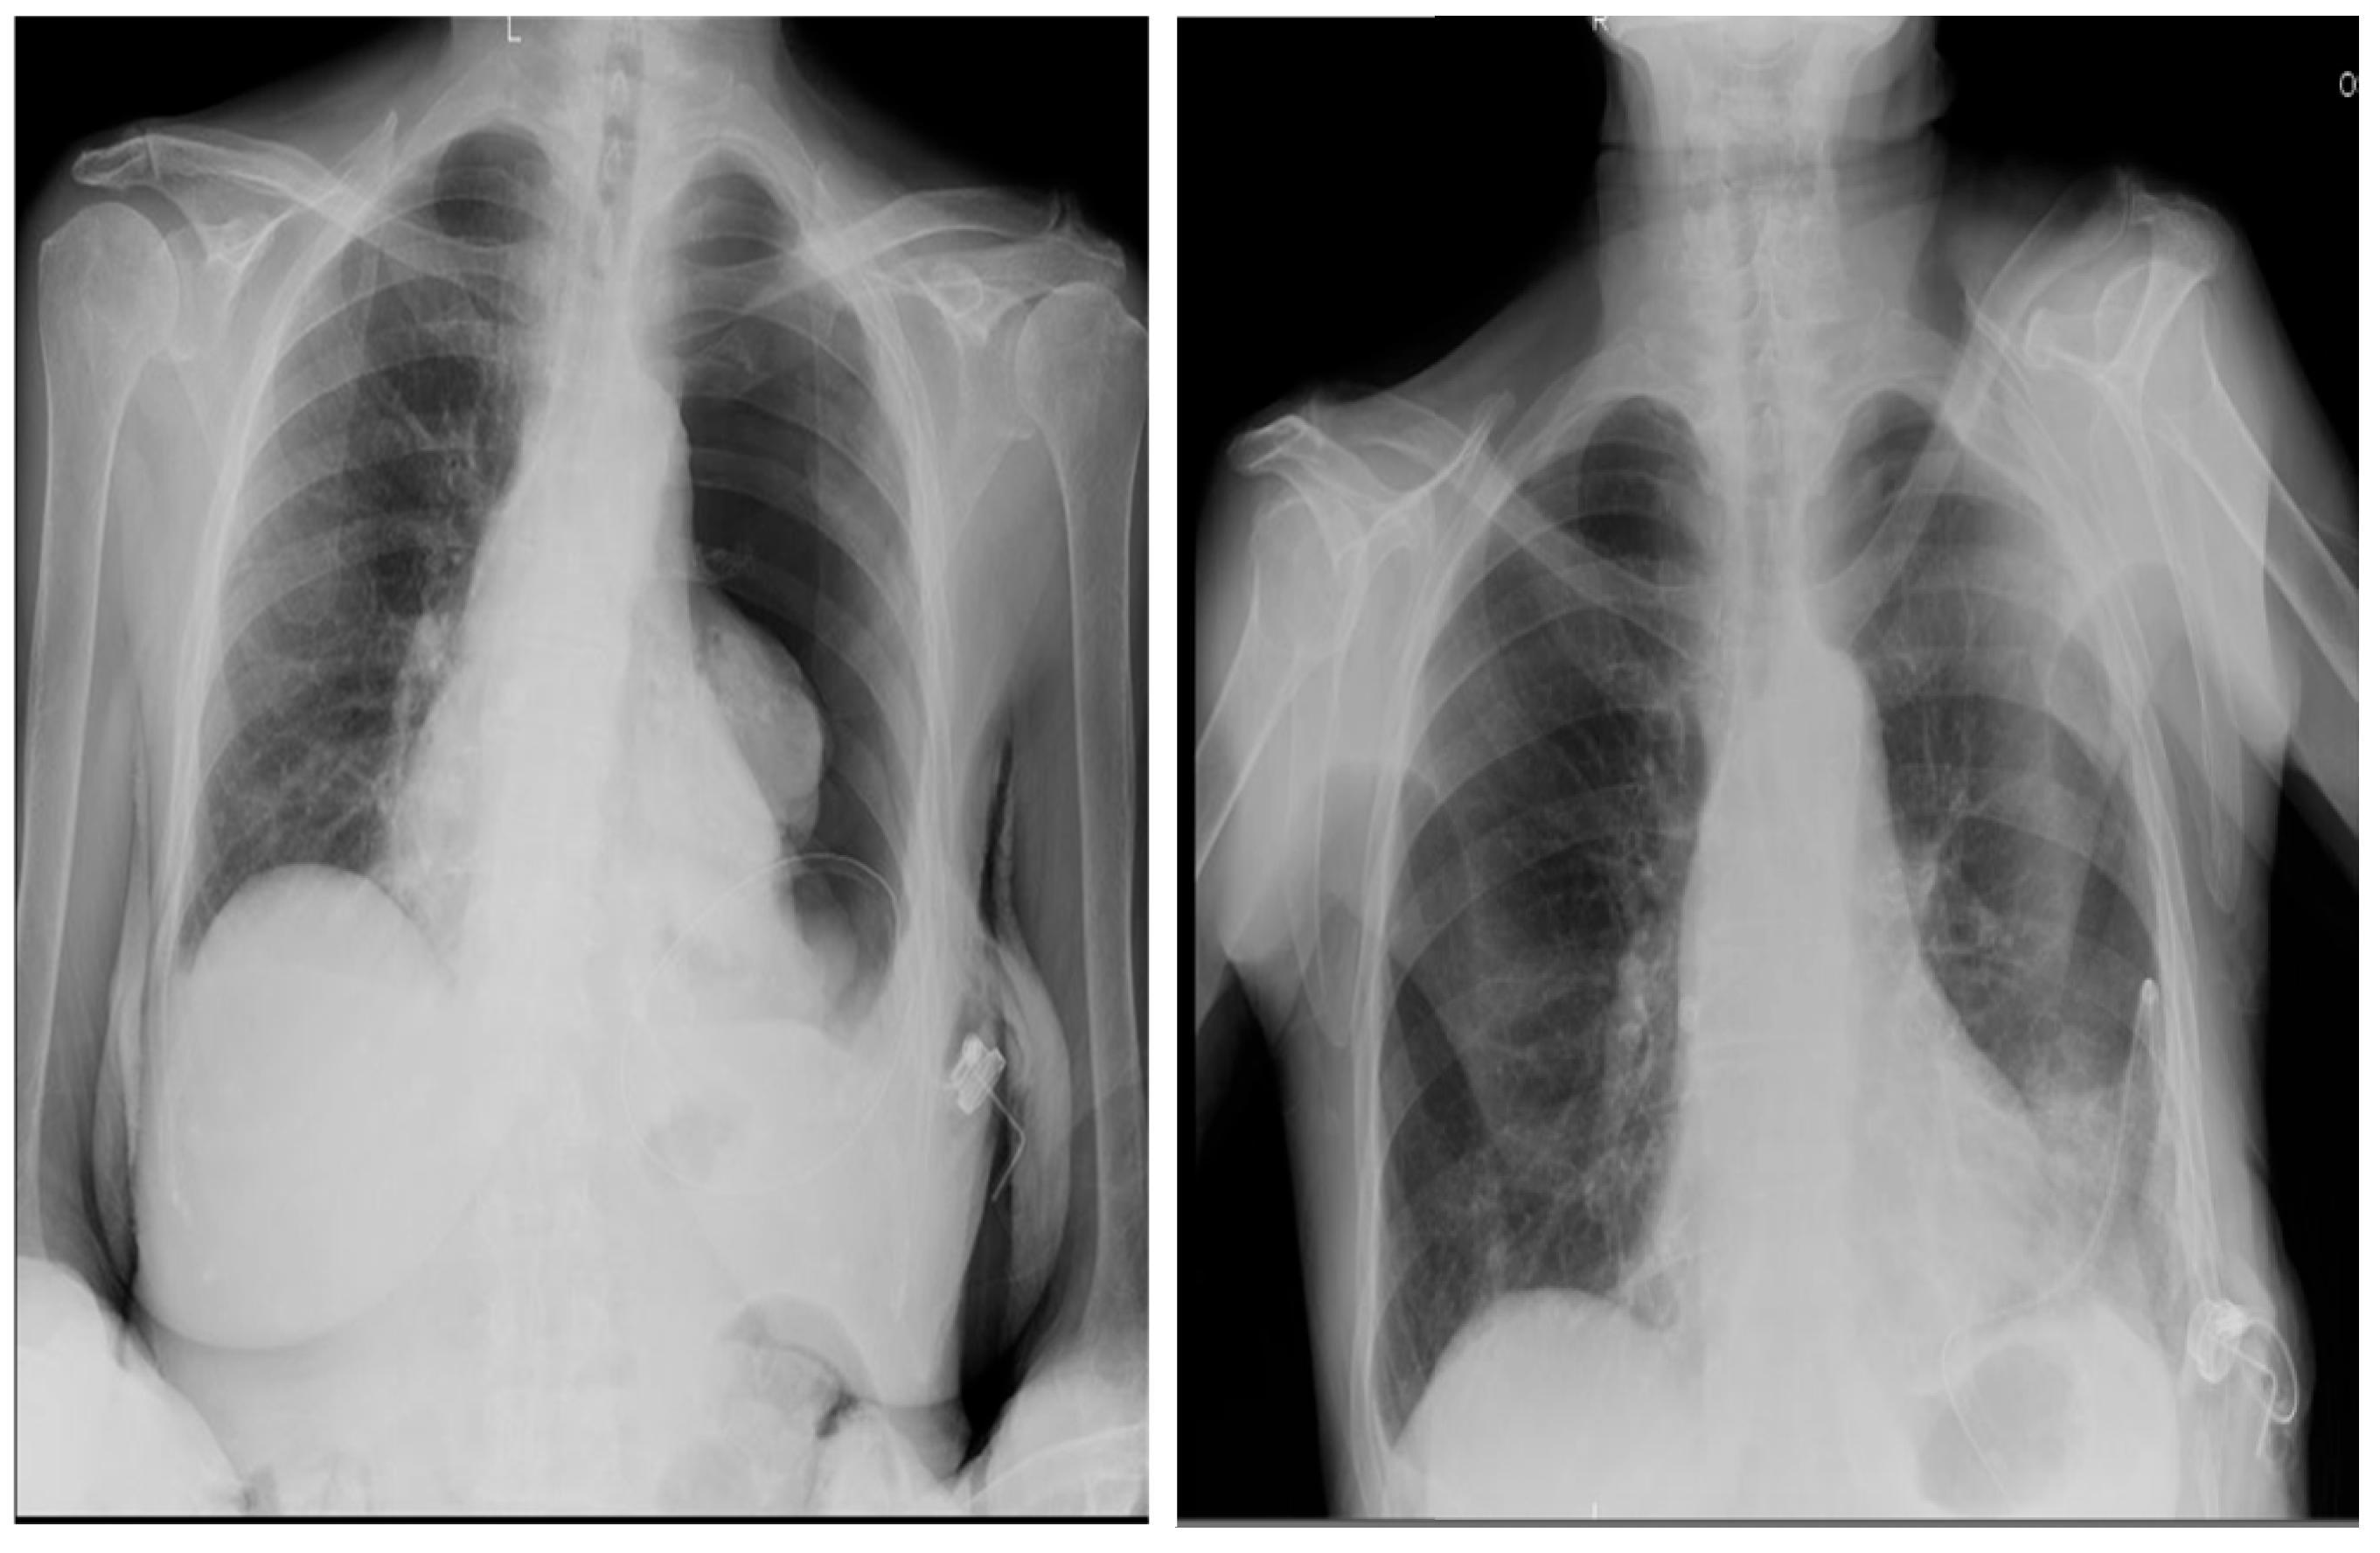

Out of 150 patients, there was a single case in which the drainage tube was implanted in the abdomen (Figure 7) and only one case of total post-implantation pneumothorax, as shown by Figure 8-A and 8-B, which however didn’t require an additional chest drainage tube and was resolved by connecting the port to a digital suction system. During follow up 18 (12%) patients developed complications (Table 3), mainly in the trapped lung sub-group (9%), with malfunction (and thus failure) of the device and wound dehiscence as the most represented ones.

Figure 8. (A) Chest X-Ray scan of a total left pneumothorax after Celsite® DRAINAPORT implantation in a 91-year-old female patient, affected by malignant pleural mesothelioma. The port was connected through a 19G gripper to a digital suction system, with a suction pressure of -20 cmH2O; (B) Chest X-Ray scan after 24 hours of suction which shows the complete resolution of pneumothorax.